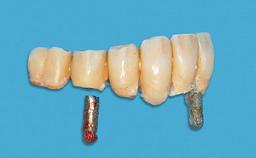

Prosthesis Type RDP

Prosthodontic SAC classification

SAC Level Advanced

Defining Characteristics Fully edentulous lower jaw to be rehabilitated with an implant-borne removable overdenture

Loading Protocol Conventional/early